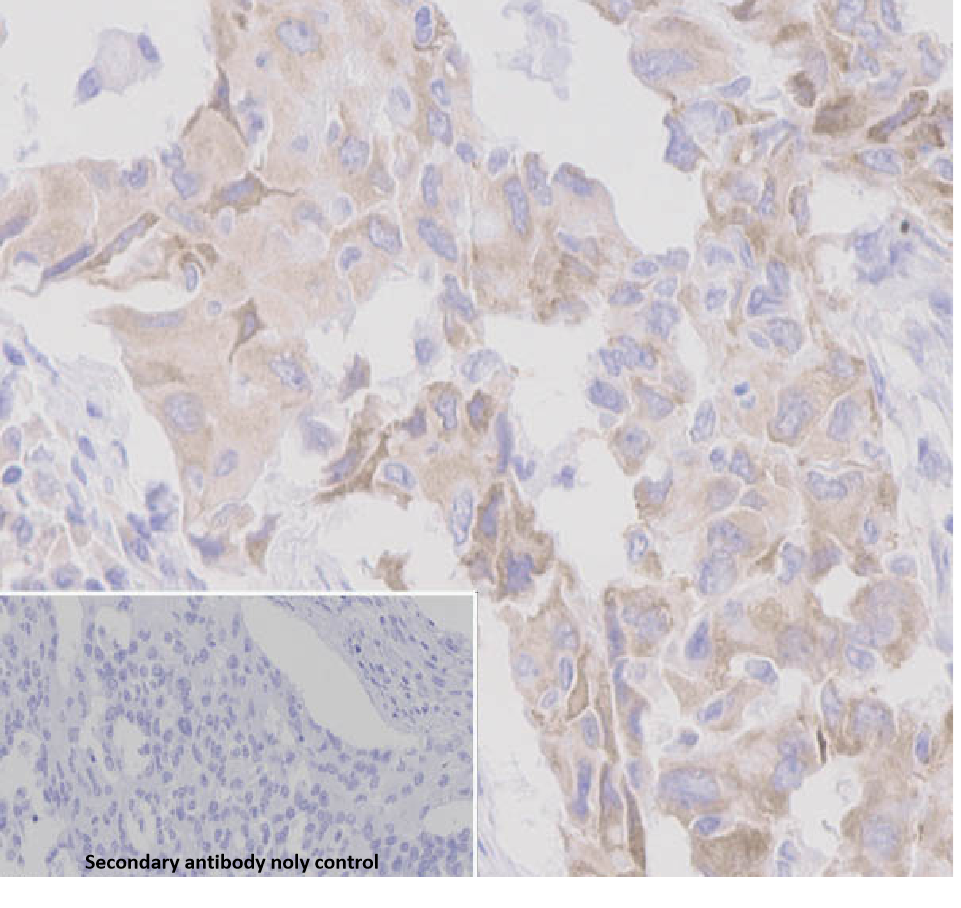

Positive control: Lung cancer

ROS1 antibody reagents can specifically bind to the ROS1 molecular antigen. Immunohistochemistry kits containing ROS1 antibody reagents are suitable for the precise diagnosis of ROS1 fusion gene-positive non-small cell lung cancer.